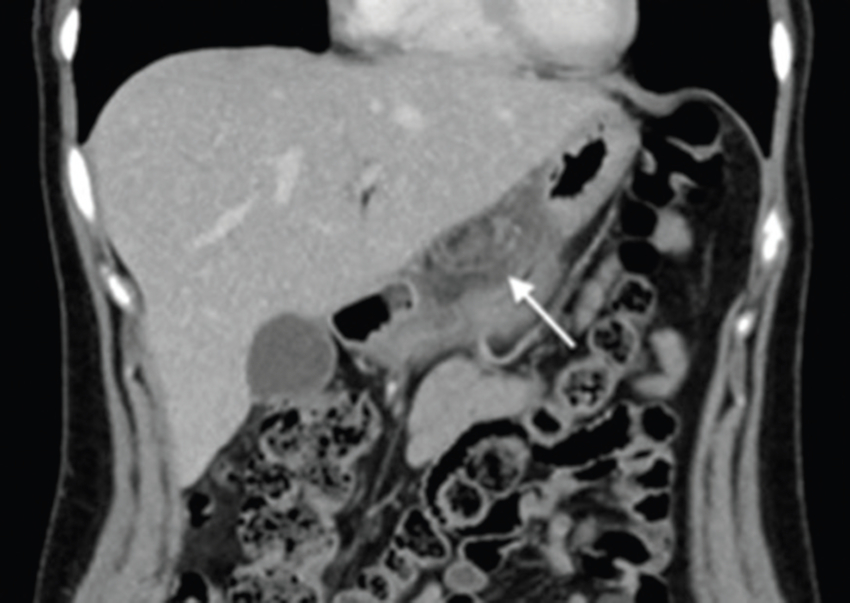

Comunicamos el caso de una mujer de 29 años, sin antecedentes mórbidos de importancia, que consultó por un cuadro de 24 horas de evolución de distensión abdominal y dolor epigástrico, que luego se hizo difuso, sin fiebre. Al examen físico destacaba dolor a la palpación abdominal, preferentemente en el hemiabdomen superior. Se le realizaron exámenes de laboratorio en los que solo se objetivó elevación de la proteína C reactiva con un valor de 14,3 nmol/l. Se decidió estudiar el dolor abdominal con una ecografía, en la que se identificó un área de tejido ecogénico lobulado, relativamente bien delimitado, situado entre el páncreas y la cara posterior del cuerpo y del antro gástrico (Fig. 1), compatible con un proceso inflamatorio del tejido adiposo peripancreático cuya etiología no se precisó. Ante estos hallazgos, se decidió complementar el estudio con una tomografía computada (TC) de abdomen y pelvis con contraste, en la que se confirmó la presencia de un aumento de la densidad del tejido adiposo comprendido entre el páncreas y el estómago, específicamente adyacente a la curvatura menor del estómago y pared posterior (Figs. 2 y 3). El tejido adiposo en relación con la mayor parte de la curvatura mayor presentaba densidad normal. Ante estos hallazgos, se diagnosticó un infarto del epiplón menor, sin signos de complicación, por lo que se decidió manejo con analgesia y controles seriados. La paciente tuvo una evolución favorable con un control a los dos meses con una nueva TC de abdomen y pelvis con contraste, en la que se observó una marcada disminución del aumento de volumen y densidad del omento menor en comparación al examen previo (Fig. 4).

La presentación clínica generalmente es dolor abdominal con sensibilidad y algunas veces con signos de irritación peritoneal. Las pruebas de laboratorio generalmente muestran una elevación leve de los parámetros inflamatorios. El diagnóstico clínico inicial depende de la localización de dolor y generalmente dentro de los diagnósticos diferenciales destacan la apendicitis, la colecistitis y la diverticulitis3,4,5,6. Ecográficamente, la presentación clásica es la de una masa sólida, moderadamente hiperecogénica, no compresible y que se encuentra en íntimo contacto con el lóbulo hepático izquierdo, páncreas y estómago, los cuales no presentan alteraciones. En TC, la presentación es de una masa inflamatoria con densidad adiposa, bien circunscrita, rodeada de órganos normales3,4,5,6,8.